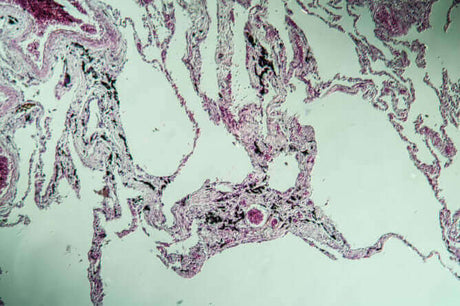

Da so ziemlich jeder Mensch im urbanisierten Raum mit Asbest in Kontakt kommt stellt sich für viele die Frage, welche Folgen für die eigene Gesundheit bestehen und wie man eventuelle...